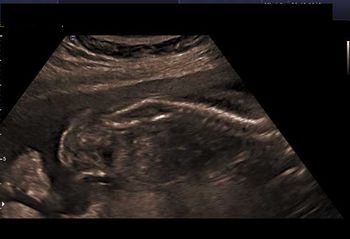

At 34 weeks’ gestation, a pregnant woman underwent a routine ultrasound examination. The findings revealed an unusual anomaly. Can you identify it?